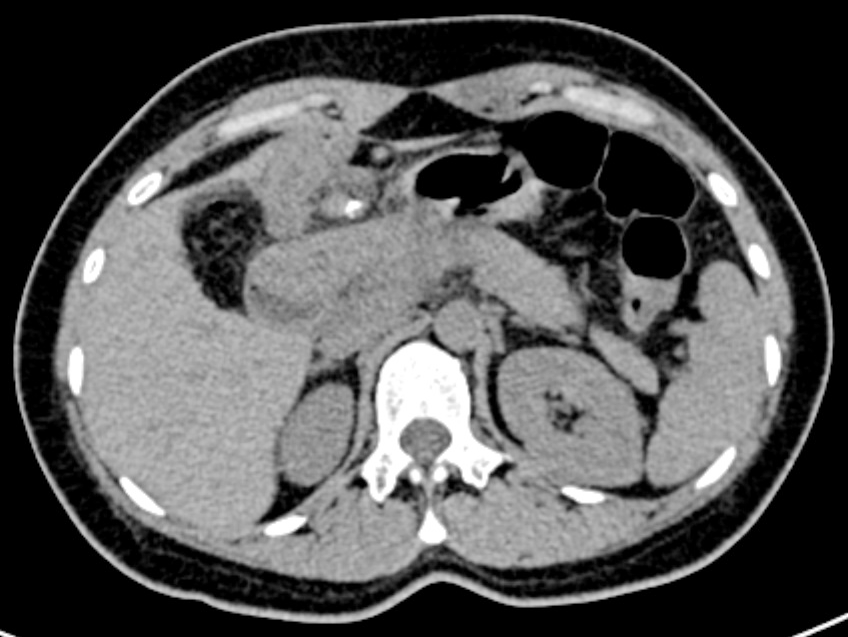

手术过程顺利,术中精准剥离囊肿并重建胆道,出血量不足50ml。得益于腹腔镜技术的精细化操作,陈女士术后第一天即可下床活动,胃肠功能恢复迅速,术后三天拔除引流管。病理检查排除恶变,印证了手术时机的科学性。住院期间,医护团队通过加速康复外科(ERAS)理念管理,结合早期肠内营养支持及阶梯式镇痛方案,术后第五天各项指标均正常,切口愈合良好,顺利出院。

▲术后复查CT检查图片及病理报告

如今,陈女士已回归正常生活,定期随访显示胆肠吻合口通畅无狭窄。这个案例也印证了成人先天性胆管囊肿通过规范化手术可获得根治性疗效,微创技术与围术期管理的进步正不断改写这类疾病的治疗体验。